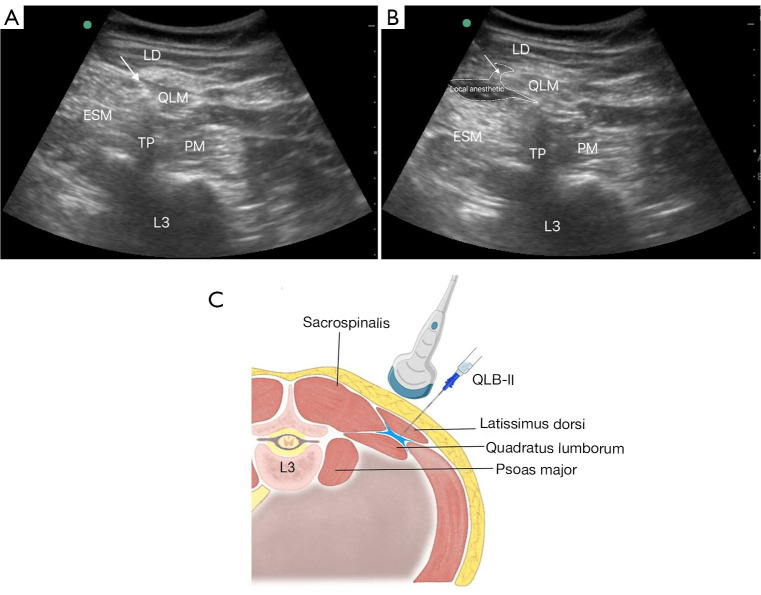

Methods: In this randomized, double-blind trial, 54 patients scheduled for laparoscopic nephrectomy were allocated to receive either ESPB or QLB with 25 mL of 0.4% ropivacaine under ultrasound guidance. Postoperative analgesia was managed using morphine-based patient-controlled analgesia. The primary outcome was cumulative morphine consumption within 6 hours postoperatively. Secondary outcomes included pain scores, morphine pump activations, the 15-item Quality of Recovery scale (QoR-15) scores, and length of hospital stay.

Abstract Image